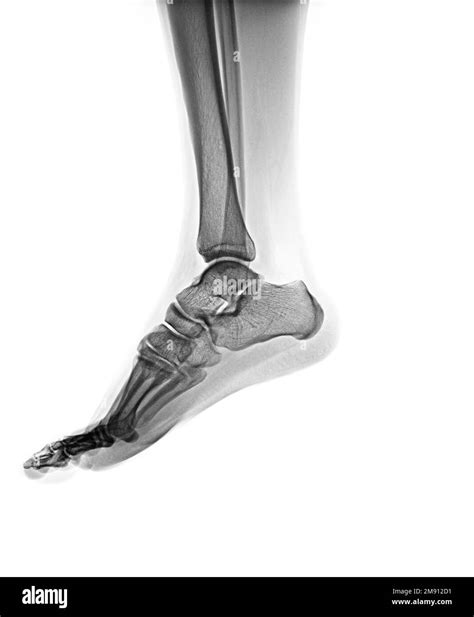

The patient is positioned on the X-ray table, and the foot is placed in a specific position to capture the desired views. Common views include:

• Lateral view: Shows the side of the foot.

Interpreting a Normal Foot X Ray involves a thorough examination of the images to ensure that all structures appear normal. Key areas of focus include:

Bones

The bones of the foot, including the tarsals, metatarsals, and phalanges, should be clearly visible and aligned properly. Any fractures, dislocations, or deformities would be immediately apparent.

Joints

The joints between the bones should be smooth and well-defined. Any signs of arthritis, such as bone spurs or joint space narrowing, would indicate an abnormality.